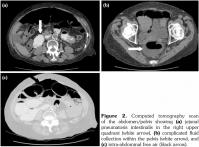

An abdominal computed tomography (CT) scan revealed large volume intra-abdominal free air, moderate intra-abdominal free fluid with no extravasated contrast, pneumatosis of the proximal jejunum with dilatation up to 5.8 cm, and a transition point (Figure 2). These findings raised concern for acute bowel ischemia, volvulus, and possible perforation.

However, given the patient’s comorbidities, stable condition and lack of peritonitis, the general surgeon recommended conservative management with intravenous fluids and bowel rest. A repeat CT scan on post-admission day two revealed resolution of the pneumatosis and focal volvulus, but persistent intra-abdominal free air and free fluid. She was started on oral amoxicillin and metronidazole for possible SIBO and discharged on post-admission day three. She was reviewed in clinic shortly thereafter, at which point her clinical condition remained stable.